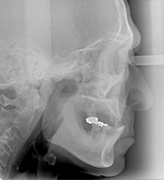

←入れ歯の装着効果を評価します.

(噛み合わせの高さが上がり,口元が適切な状態に)

↓義歯の設計にあたっては,セファログラム(規格化)

レントゲン分析も併用して問題点を診査します.

軟組織分析(口元突出・口角・E-ライン・オトガイの筋緊張・気道の大きさ),骨分析(下顎関節の位置・頚椎の

湾曲度・下顎の回転度,咬合平面角,かみ合せの高さ)